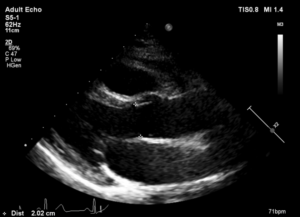

马凡综合征患者最先表现的是主动脉根部的扩张,那什么是主动脉根部呢?主动脉根部是连接左心室和升主动脉重要组成部分,相当于心脏的一个“出口”,主要是由主动脉瓣环,窦部及窦管交界组成(图1),马凡患者早期表现为主动脉窦明显扩大,呈“蒜头样”或“梨”形,在超声上主要表现为单独的窦部增宽(正常成人<3.5cm)(图2),或者整个根部(瓣环、窦部、窦管交界)增宽,甚至扩张(图3),有时在超声图像上可见窦管交界消失并伴随着升主动脉的扩张。正常患者当根部>5.5cm时就建议手术治疗,而马凡综合征的患者则在根部>5.0时建议手术治疗。

图2.主动脉窦部增宽>3.5cm

图3.主动脉瓣环、窦部、窦管交界均增宽